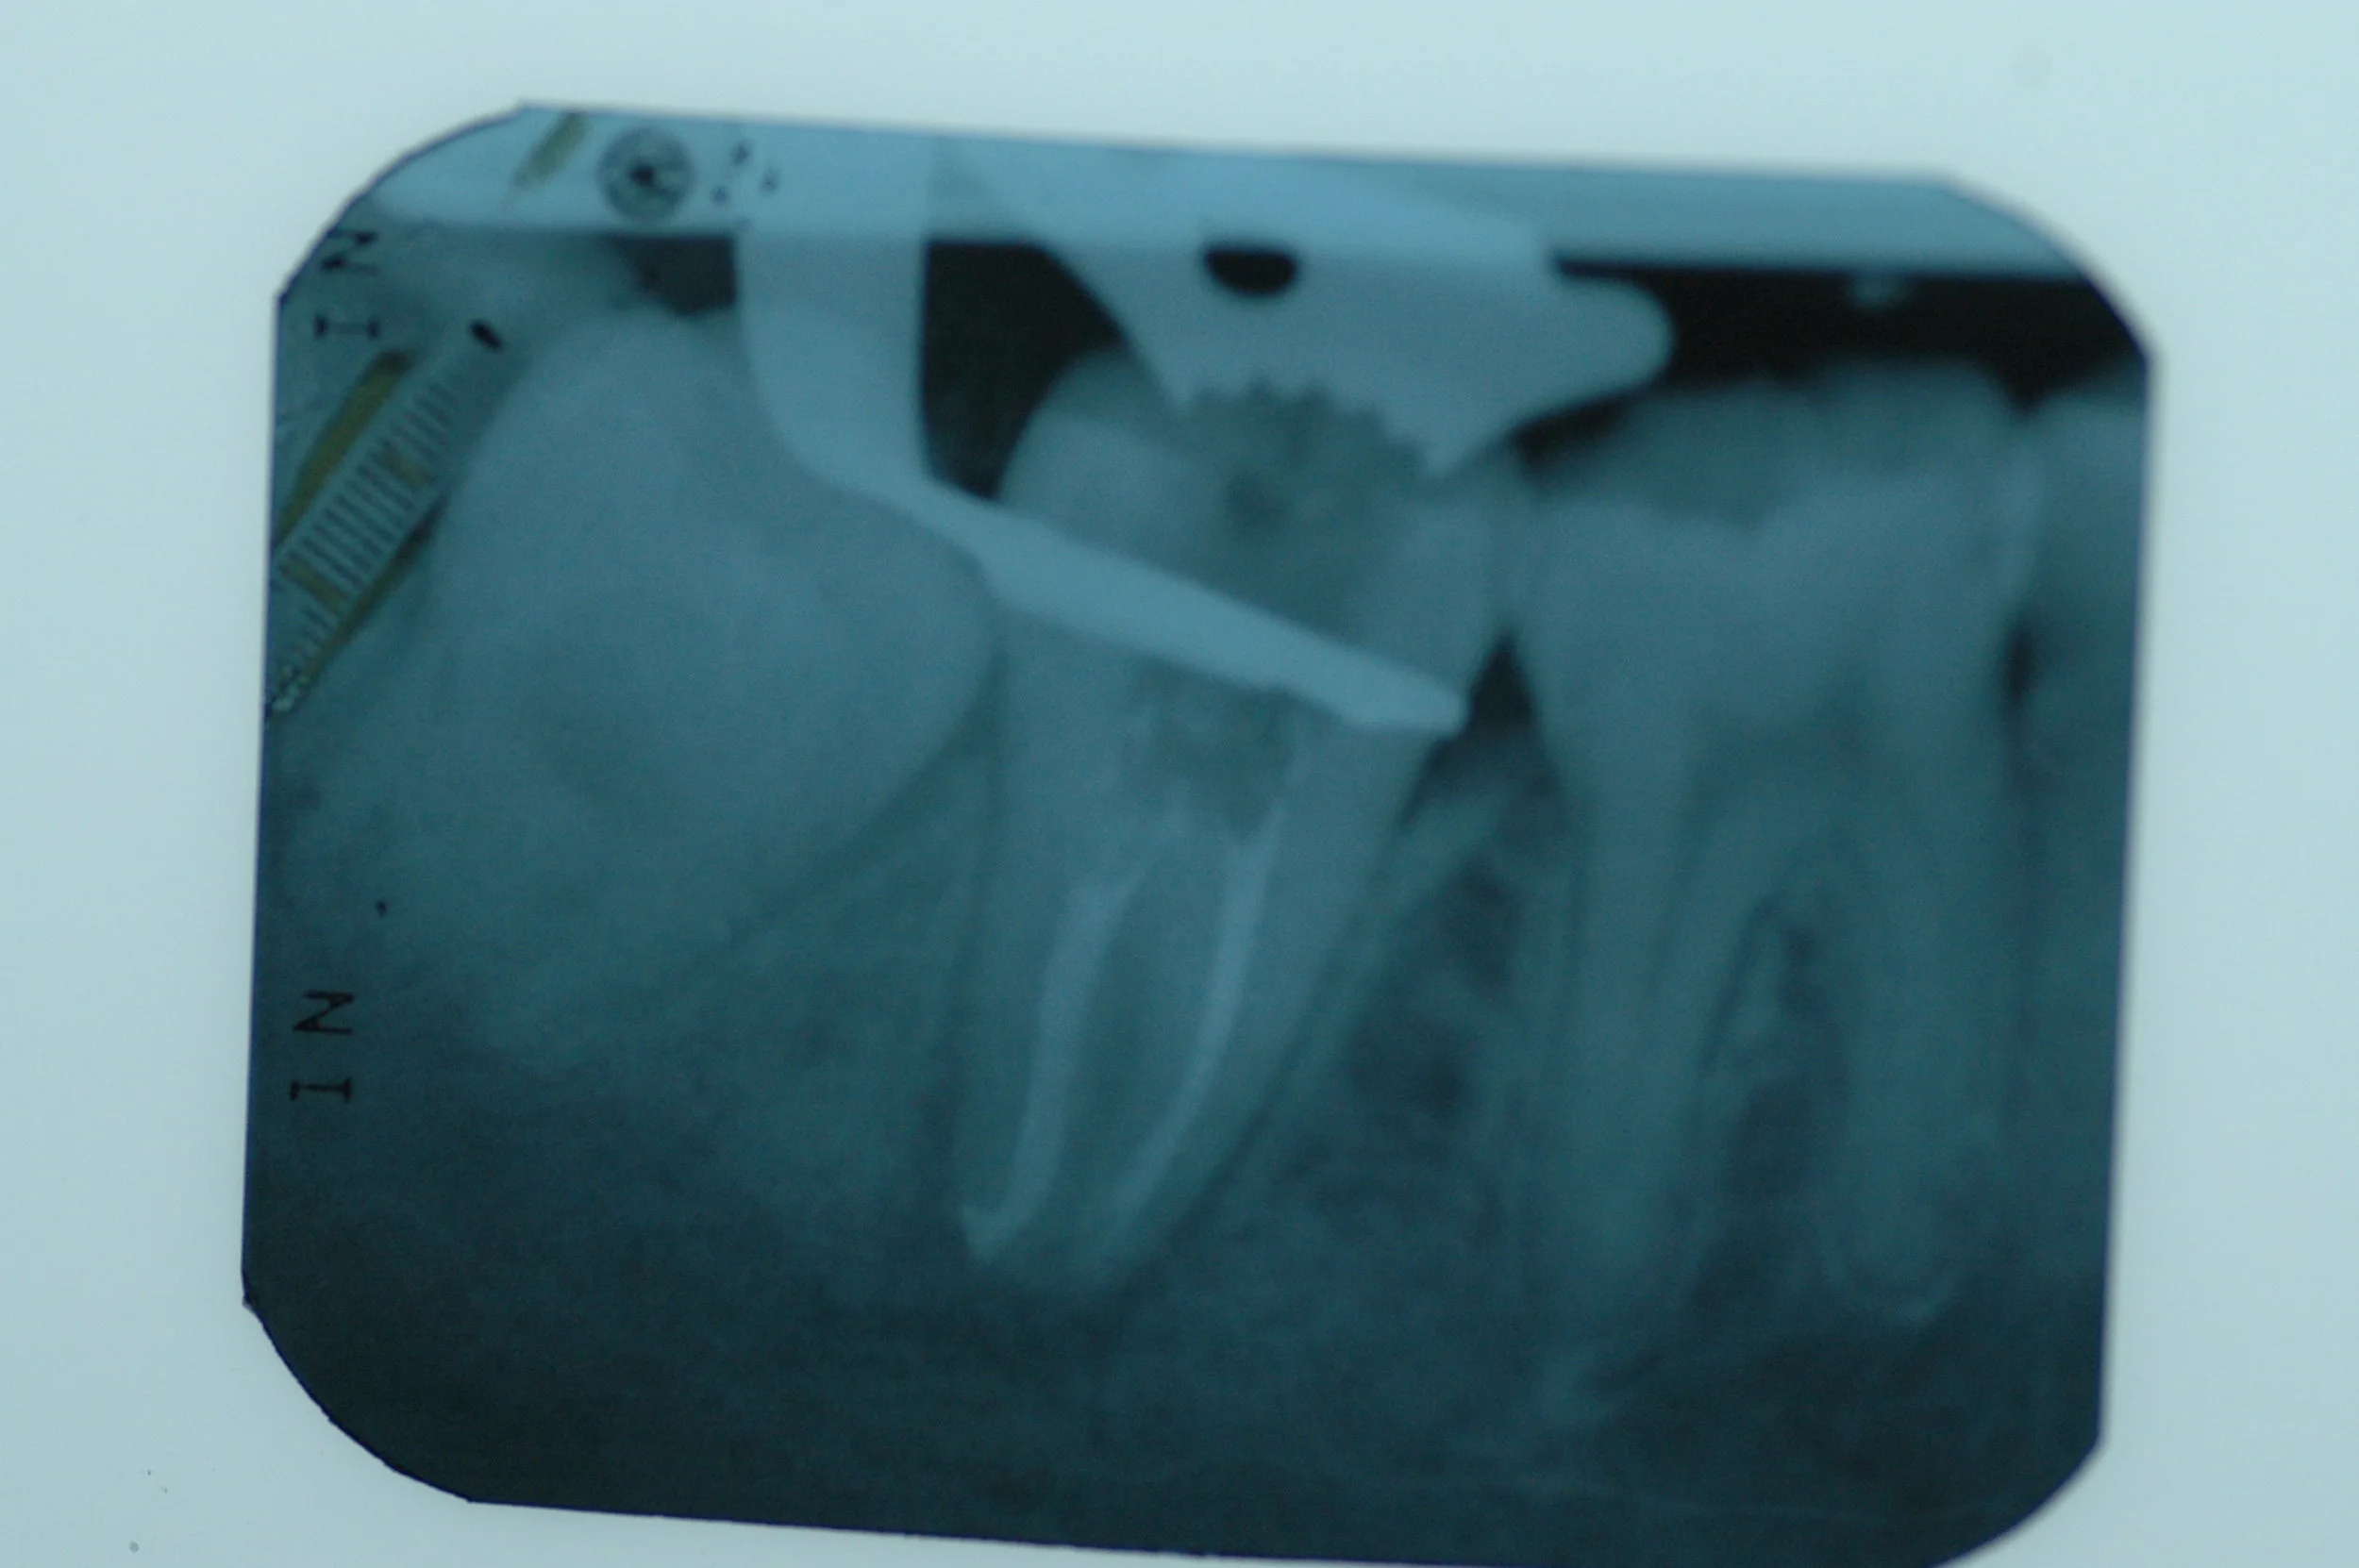

Complex Root System

Lower Premolar